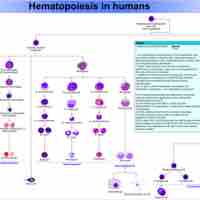

The immune system includes primary lymphoid organs, secondary lymphatic tissues and various cells in the innate and adaptive immune systems.

The immune system protects organisms from infection first with the innate immune system, then with adaptive immunity.

The lymphatic system houses large populations of immune cells which are released upon detection of a pathogen.

Adaptive immunity is stimulated by exposure to infectious agents and recruits elements of the immunoglobulin superfamily.

Clonal selection and tolerance select for survival of lymphocytes that will protect the host from foreign antigens.